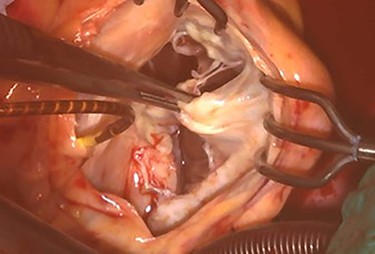

An 81-year-old male presenting with a PM pocket-associated infection was referred to our institution. Twelve years prior, a conventional PM was implanted for bradycardia and atrial fibrillation. A pocket infection was noted after the device generator was changed one month prior. We performed a complete pacing system extraction, but during explantation of a transvenous lead via simple traction, myocardial tissue adherent to the lead was concomitantly removed. Subsequently, the patient developed ventricular fibrillation. An immediate transthoracic direct-current cardioversion resulted in successful defibrillation. Postoperative transthoracic echocardiography (TTE) revealed tricuspid valve destruction and severe regurgitation (Fig. 1). A hasty surgical repair of the tricuspid valve or implantation of new transvenous leads seemed undesirable at the time because of ongoing active endocarditis. In addition, with the hope that the patient could tolerate severe TR as he had moderate TR preoperatively secondary to his PM lead, we considered a leadless transcatheter pacing system, Micra implantation without tricuspid valve repair. Micra implantation procedures went well, and after sufficient antibacterial therapy, the patient was discharged stable (Fig. 2A).

Intraoperative photograph; septal and posterior leaflet of tricuspid valve are severely damaged.